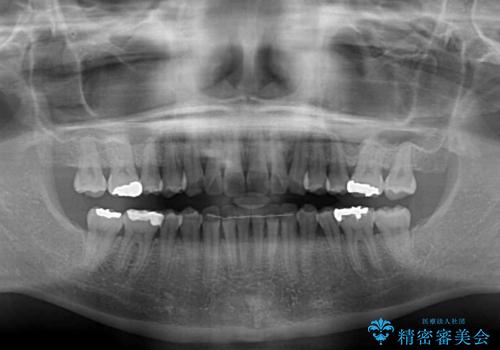

- 前歯のデコボコを気にして来院された患者様です。

歯列不正が軽度であり、インビザラインの装着時間を遵守してくださったため、日本と海外を行き来しながらも2年弱でしっかりと仕上げることができました。